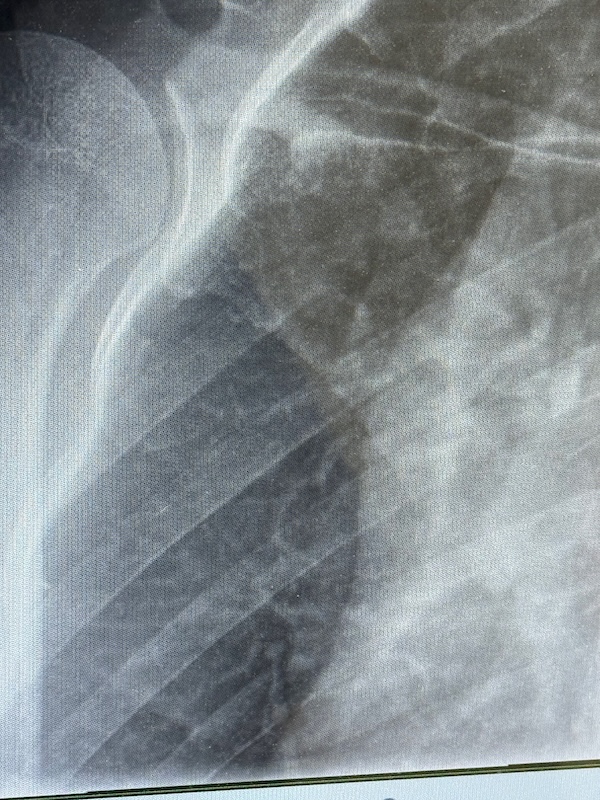

Ik zie Rob aankomen en pak mijn spullen. Het lukt allemaal, maar de pijn is groot. Ik kan door veel pijn heen, dat ben ik gewend, maar ik denk dat dit een verrekking is. Ik kan appen. Met links. We rijden naar de huisarts en wachten weer een kwartier. Ze ziet niks, maar mijn pijn is te groot. Ze denkt aan een pees scheurtje. Door voor een foto naar het ziekenhuis. De huisarts kent triatlon wel! In het ziekenhuis kan ik pas na 5 uur bij de huisartsenpost terecht voor een röntgenfoto. Even thuis langs voor een paar koekjes en wat drinken. Zelf een fles open maken lukt me niet. Rob appt en Vincent ook. Die gaat naar een terras. We zien een paar collega’s nog op de parkeerplaats: jo, jef en ma. Ik vind het ziekenhuis moeilijk. Ik haat deze plek. De huisartsenpost gaat net open. Ze lopen mee naar radiologie. Er worden 3 foto’s gemaakt. Ik mag mijn shirt aanhouden. En dan weer wachten. Ik moet de hele tijd plassen. En dat is lastig met 1 hand! Is dat een reactie van het lichaam, dat vele plassen? Er komen wat andere mensen; 1 meneer grapt dat hij zijn duim er met het stanleymes niet af kreeg. Ik snap die reactie wel: het heeft geen zin om te sippen, ik voel me ook nog vrolijkjes. Maar pijn hebben kost veel energie. Ik kan het echt allemaal minder goed snappen. Vincent komt ook. En dan worden we opgehaald. Na een uur. Ik raak het besef van tijd kwijt. Ze zegt: slecht nieuws he, dat ik je ophaal. Ik heb een breukje in mijn schouder. Dat komt hard aan. Zolang ik zat, voelde het beter. We lopen binnendoor naar de spoedeisende hulp. Er wordt verbouwd. Daar moet ik me melden. Een grappig vriendelijke mevrouw meldt dat het druk is en ik krijg een bandje. Tering, wat is er joh! Ze verifiëren mijn gegevens. Weer even wachten en dan een screening plek. Ze vragen wat ik heb gedaan en gokken op vallen met de fiets. Het is veel stommer dan dat! Ik leg ze uit en ze kijken even en ik krijg 2 paracetamols. Het dringt door dat dit lang gaat duren. Langer dan een week IJsselmuiden missen, zelfs mei lijkt afgeschreven. Pas als Rob en Vincent er bij komen vertellen we over triatlon. Weer een wachtkamer vol mensen. Ik kan het wel aan Vincent vertellen. Maar deze plek is nóg erger! Dokter Martijn haalt ons op. Hij laat de foto’s zien en gelukkig had ik Rob al gevraagd foto’s te maken van de foto’s.

Ik zie het niet zo heel goed. Ik hoor het: 3 weken niet sporten. Het moet weer aan elkaar groeien. Zelf. April en mei afschrijven. Geen triatlons. Binnen fietsen. Om wat conditie vast te houden. Niet hardlopen. Dat is zwaar voor een verslaafde! Over een week terugkomen. Ik krijg een sling. Ik update Jef en Ma en Jo zijn er bij en appen me ook. Joyce had ik al geappt voor de röntgenfoto. Die baalt met me mee. De dokter gaat vragen of een mri nog nodig is. Gelukkig niet. Ik krijg die sling, maar voor mij helpt het niet echt. Ik vraag hoe ik moet slapen en de dokter zegt: ogen dichtdoen 😆 ook over werken kan hij weinig zeggen. Ik ben blij dat er echt iets is en niet zomaar pijn. Maar ja, juist dat er iets is is erg pijnlijk. Hij helpt me met de sling, maar dat is vooral dat je ziet dat er iets is en dat rechts gefixeerd is. We lopen weer naar de auto en ik heb trek en pijn.  Dat het triatlonjaar voorbij is voor de eerste triatlon is pijnlijk. Ik heb mijn zorgbudget opgebruikt! We eten frietjes. Ik dek de tafel met links. MvdB belt me direct, de schat. De trainster is net even niet bereikbaar helaas. Ik bel de ouders. Ik had gelukkig de stappen gehaald. Rechtop zitten gaat nog het beste. Dat alle scherpte weg is merk ik wel bij het rummikuppen. Alsof ik er niet helemaal bij ben terwijl ik er erg van geniet. Ik schrijf het van me af. Op voor een lange nacht en het accepteren van een hoop verlies.

Ik heb mijn rechter schouderblad gebroken.

10 april. Een bedrijfsfeestje. Survivallen. Een stormbaan met een netje nog geen meter boven de grond. Ik ben verkeerd gevallen. Precies fout. Pijn, misselijkheid, toch maar naar de huisarts, foto’s in het ziekenhuis. De rest van april draag ik een sling om er voor te zorgen dat ik mijn rechterarm niet gebruik. De breuk moet zelf genezen. Met rust. Niet fietsen (al kan binnen wel), niet hardlopen en met zwemmen kan ik waarschijnlijk pas over 6 weken weer beginnen.

Uitleg gekregen: het schouderblad is inderdaad heel flink gebarsten zeg maar. Goed gebroken. Na 3 weken is het weer aangegroeid. Herstel tot wat ik kon kan tot een half jaar duren. Hij heeft het aangewezen en uitgelegd dat de frictie en wrijving pijnlijk is als ik mijn arm boven 90 graden til. Als hij het aanwijst, voel ik daar niks van. Het zit hoger dan ik dacht.

Wat ik niet kan is dus als die breuk langs de borstkas draait. Dan doet het zeer. Als ik dat toch doe, verergert de breuk niet.